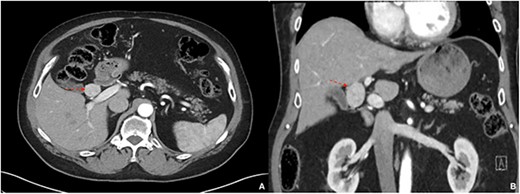

A 77-year-old male with a history of hypertension and hypothyroidism underwent imaging for possible fatty liver disease and was found to have a 3 cm porta hepatis mass causing mild intrahepatic biliary ductal dilation on Magnetic Resonance Elastography (Fig. 1). A multi-phase computed tomography (CT) obtained and showed an isolated 2.8 cm hyperenhancing nodular mass in the liver hilum (Fig. 2). The patient did not have any symptoms, such as jaundice, vomiting, flushing or diarrhea. Physical examination and all biochemical markers were normal, including liver function tests and serum tumor markers (alpha-fetoprotein and carcinoembryonic antigen 19–9). No serologic evidence of hepatitis B or C virus infection was found.

A multi-phase CT showing a 2.8 cm hyperenhancing nodular mass in the liver hilum; (A) axial view, (B) coronal view.